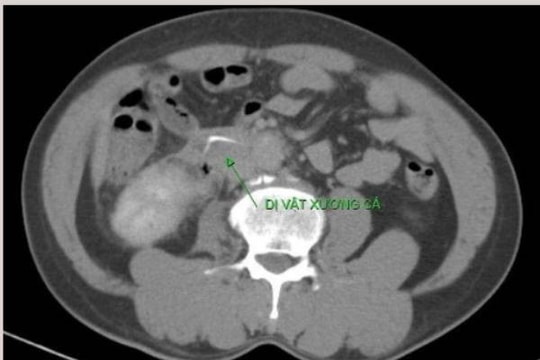

Người đàn ông 55 tuổi ở Phú Thọ bất ngờ bị thủng ruột sau khi ăn cơm cá

Đi khám vì đau bụng, người đàn ông ở Phú Thọ được phát hiện có dị vật đường tiêu hóa xuyên thủng thành ruột. Bác sĩ nghi ngờ dị vật là xương cá từ bữa ăn trước đó.

Cấp cứu thành công bệnh nhân thủng ruột do nuốt xương cá

PLBĐ - Xương cá nằm trong ổ bụng của bệnh nhân 52 tuổi, đâm thủng ruột non dẫn đến tình trạng viêm phúc mạc.